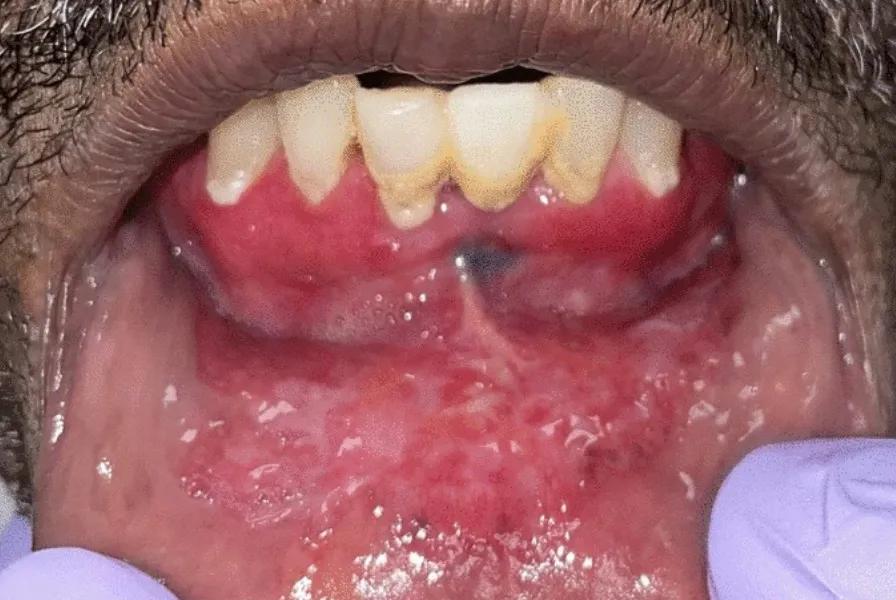

View of lower lip showing EMPD

Above: Paget cells exhibit markedly atypical nuclei with abundant amphophilic cytoplasm. Top of page: Extensive red/white mucosal change of anterior mandibular vestibule and lower lip concerning for lichenoid inflammatory process or dysplasia/carcinoma. Both images reprinted from Dababneh et al, Head Neck Pathol. 2024;18[1]:33, under the Creative Commons CC BY license. © The Authors